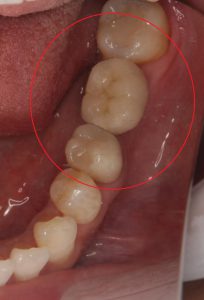

【術後】

両隣の歯を削ることなく、治療を行うことが出来ました。

今後も定期検診で歯を守っていきましょう!